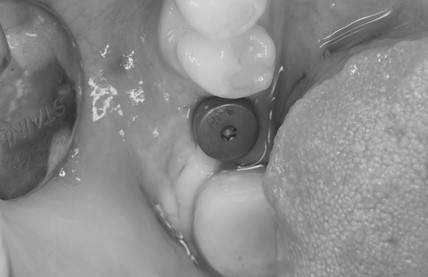

症例写真-1

- Befor

- After

症例写真-2

- 途中経過

| 年齢 | 50代・男性 |

| 主訴 | 右下歯が疼く |

| 治療内容 | ・右下6番インプラント ※1:FGG(遊離歯肉移植術)とは、足りない歯ぐきを上顎から上皮を切り取り移植する外科手術 |

| 治療費 | 合計:902,000円(税込) ■内訳 |

| 治療期間 | 9ヵ月 |

| 治療方針 | 右下の当該歯は歯根破折により保存不可能と診断しました。歯周疾患も伴っていたため抜歯後に骨吸収※1が大きく起こることが予測できました。チタンメッシュ併用骨再生誘導法(GBR※2)を選択しインプラント埋入と同時に行い自然な歯槽骨のラインを再現しました。またGBRを行う際にインプラント辺縁の付着歯肉の減少が起こる為、遊離歯肉移植術(FGG※3)を行い清掃性を考慮した形態に仕上げました。 ■治療方針の解説 治療した右下の歯をレントゲンで撮影したところ根本の部分に黒く写る箇所があり「根尖性慢性周囲炎※1」と診断。また歯周病も進行していました。 ※1 骨吸収・・・歯槽骨という歯を支える骨がなくなっていくこと |

| 担当者所見 | 主訴の右下だけでなく歯茎の腫れ、発赤があり不良補綴や不良充填など他にも治療箇所が多数ありました。プラークコントロールが不良であった為まずはブラッシング指導を行いセルフケアの重要性を理解していただくところからスタートしました。 右下6番の歯はインプラント治療を行なった結果審美的にも機能的にも患者様の満足を得ることができました。骨造成と歯肉移植も行なった為インプラントを支える十分な歯周組織の獲得ができたと思っております。 |